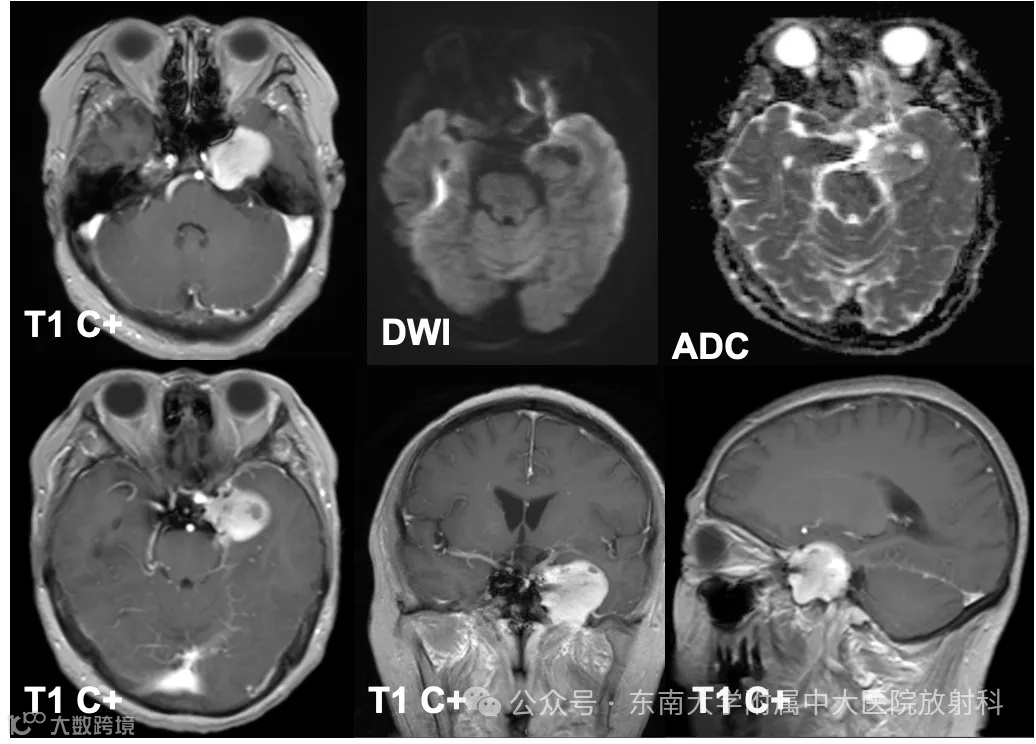

性别:女 年龄:69岁

主诉:左侧面部麻木5年余,加重伴肿胀1月余

现病史:患者5年前出现无明显诱因左侧面部麻木,至当地医院检查发现左侧鞍旁占位,予定期复查,未予特殊处理。1月前患者出现左侧面部麻木伴肿胀阵发性加重,遂至当地医院查头颅MR示:左侧鞍旁肿瘤,33x29mm,较前增大,多发陈旧性腔隙性脑梗死。头颅CT示:颅底介入术后改变。现患者为求进一步诊治至我院就诊,门诊拟“左侧鞍旁占位性病变”收住入院

既往史:自诉4年前于当地医院行脑动脉介入栓塞术

影像学表现